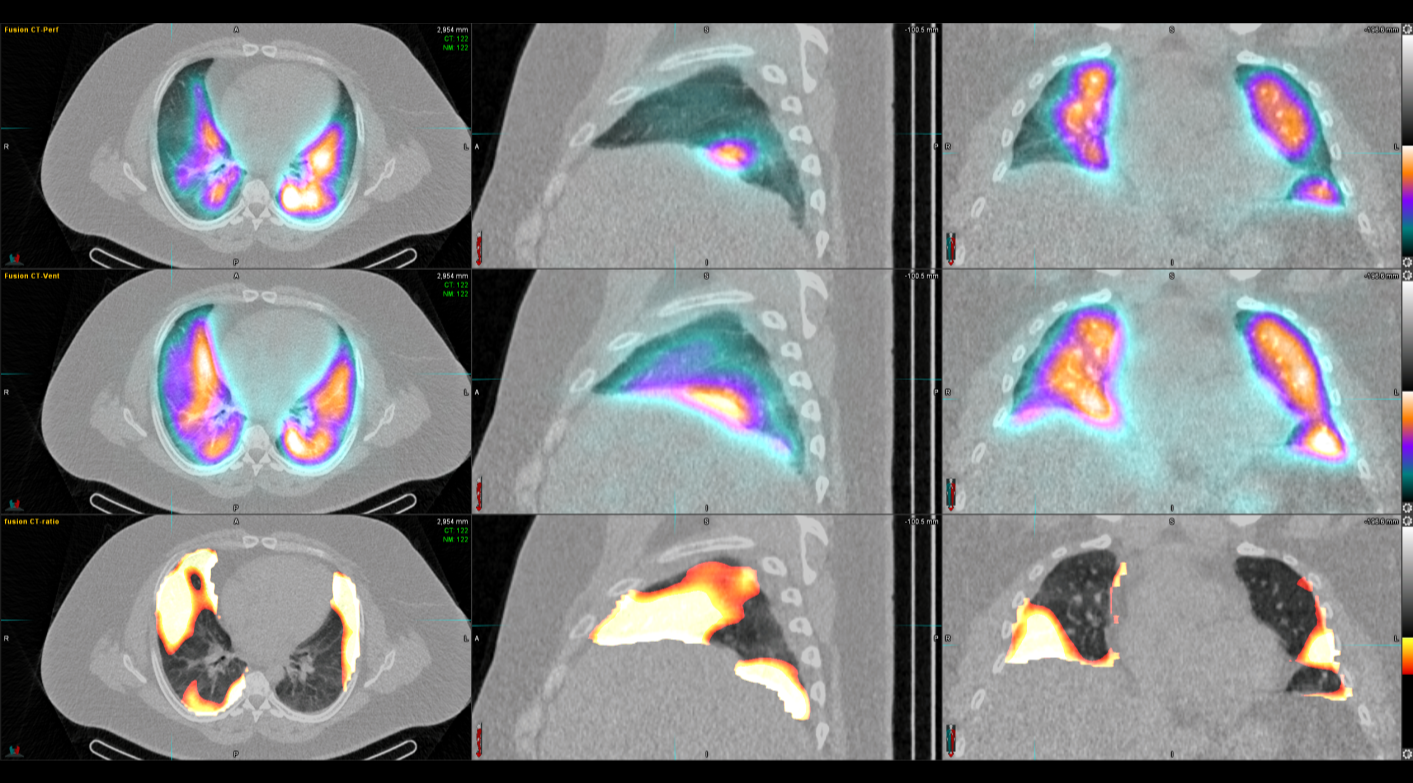

Οι περισσότερες διαγνωστικές εξετάσεις της Πυρηνικής Ιατρικής είναι γνωστές ως σπινθηρογραφήματα, τα οποία στη σύγχρονη εποχή πραγματοποιούνται με τη βοήθεια της γ-κάμερας (γ-camera) ή συστημάτων SPECT/CT, που επιτρέπουν απεικόνιση υψηλής ακρίβειας και λειτουργική ανάλυση σε μοριακό επίπεδο.

Tο Νοσοκομείο ΥΓΕΙΑ είναι το μοναδικό με πάνω από 15 χρόνια εμπειρία στην SPECT CT Aπεικόνιση. Από το 2024 διαθέτει δύο υπερσύγχρονες τομογραφικές γ-κάμερες της Siemens – Symbia Pro.specta SPECT/CT with myExam Companion. Πρόκειται για συστήματα τελευταίας γενιάς που συνδυάζουν υψηλή απεικονιστική ακρίβεια, χαμηλή δόση ακτινοβολίας και πλήρη αυτοματοποίηση της διαδικασίας. Με την χρήση ειδικού σύγχρονου λογισμικού (SIEMENS SYNGO) εξασφαλίζεται η μέγιστη ποιότητα εικόνας. Ειδικότερα οι γ-κάμερες χαρακτηρίζονται από τα εξής:

Όλες οι μελέτες Πυρηνικής Ιατρικής πραγματοποιούνται με SPECT/CT μέθοδο στις 2 υπερσύγχρονες SIEMENS Pro SPecta. Από το δυσδιάστατο στο τρισδιάστατο, από την υπόνοια στη βεβαιότητα.

Η θεραπεία με Ύτριο-90 SIR-Spheres (Y-90) αποτελεί μια εξειδικευμένη τεχνική εκλεκτικού ενδοαρτηριακού εμβολισμού, η οποία στοχεύει αποκλειστικά τον όγκο μέσω των ηπατικών αγγείων, επιτρέποντας την εναπόθεση σωματιδίων που εκπέμπουν ραδιενέργεια τοπικά με ελάχιστη ακτινική επιβάρυνση στους υγιείς ιστούς. Η διαδικασία περιλαμβάνει λεπτομερή προθεραπευτικό αγγειογραφικό σχεδιασμό με αξιολόγηση της αγγειακής ανατομίας και χορήγηση ενός ιχνηθέτη για την ανίχνευση τυχόν διαφυγής (πχ. lung shunt), εξασφαλίζοντας μέγιστη ασφάλεια και εξατομίκευση. Η επιλογή της δόσης γίνεται πλέον με σύγχρονα υπολογιστικά μοντέλα δοσιμετρίας και εξειδικευμένα λογισμικά (όπως MIM ή SIR-TeX platform), τα οποία επιτρέπουν ακριβή αποτύπωση του όγκου της νόσου στο ήπαρ, υπολογισμό του πραγματικού tumor burden και εκτίμηση της απορροφούμενης δόσης τόσο στον όγκο όσο και στο υγιές ηπατικό παρέγχυμα. Μετά τη θεραπεία, πραγματοποιείται έλεγχος κατανομής της ακτινοβολίας (μέσω Bremsstrahlung SPECT/CT ή PET/CT), ενώ ακολουθεί στενή απεικονιστική και κλινική παρακολούθηση για την αξιολόγηση της ανταπόκρισης, την εκτίμηση τυχόν τοξικοτήτων και τον σχεδιασμό επόμενων βημάτων στην ογκολογική στρατηγική του ασθενούς. Πρόκειται για μια ιδιαίτερα αποτελεσματική θεραπευτική επιλογή σε πρωτοπαθείς ηπατικούς όγκους και σε ηπατικές μεταστάσεις, ειδικά όταν οι συμβατικές θεραπείες έχουν περιορισμένη αποτελεσματικότητα ή δεν είναι πλέον εφικτές.